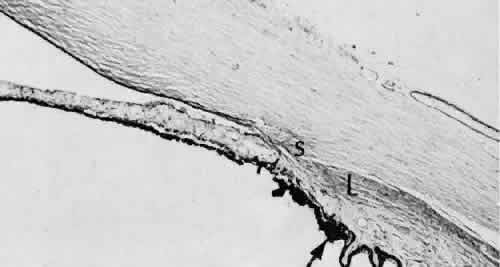

Wound healing of the neurosensory retina follows the principles of wound healing. There is an initial removal of all necrotic tissue by phagocytosis followed by proliferation of cells to form a chorioretinal bond. The healing, however, is modified in most instances by the lack of participation by the blood vessels.43–45 Astrocytes from the neurosensory retinaproliferate from the peripheral viable tissue into the wound and downward into the area of the subretinal space (Fig. 12). Retinal pigment epithelial cells from the peripheral viable tissue undergo fibrous metaplasia and proliferate upward into the area of the subretinal space. When the two proliferating cell types unite, a tight chorioretinal bond is formed. Increased retinal adhesiveness has been estimated to be 140% of the normal degree of adhesiveness 2 weeks after photocoagulation.46 Retinal holes may heal spontaneously if supported by an intact vitreous base or if located adjacent to the retinal pigment epithelium (Fig. 13).47,48 For the retinal pigment epithelium to differentiate, it must be in contact with overlying retinal pigment epithelium.49 Choriocapillaris repair from a photocoagulation wound of the retina appears to proceed in a manner similar to that of repair of capillary thrombosis in other tissues.50 The vascular repair process may not reproduce the lobular architecture of the native choriocapillaris.51 The choriocapillaris may regenerate in areas of restored retinal pigment epithelium.52 Proliferative vitreoretinopathy is an expression of abnormal retinal wound healing.53

Fig. 12. Light micrograph of an area over a retinal buckling element for retinal reattachment. Cryotherapy has been applied in the area, causing atrophy of the neurosensory elements of the retina. There is an intimate association of the remaining glial elements of the retina (R) with proliferated retinal pigment epithelial cells in the plane of the former subretinal space (arrow). The adhesion prevents intraretinal separation in this area. (Periodic acid-Schiff stain; × 100.)